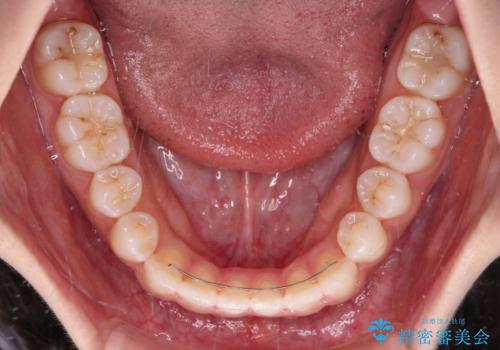

- 前歯の上下スペースと前歯の隙間を気にして来院された患者様です。

インビザラインにより上下の前歯の隙間を閉じていくこととしました。

上下の隙間に舌が入り込むことが、すきっ歯やオープンバイトの原因であったため、舌の筋肉のトレーニングも並行して行い、後戻りの抑制を図りました。

- 矯正治療後の保定が不十分だと後戻り(元の位置に戻ろうとする動き)をします